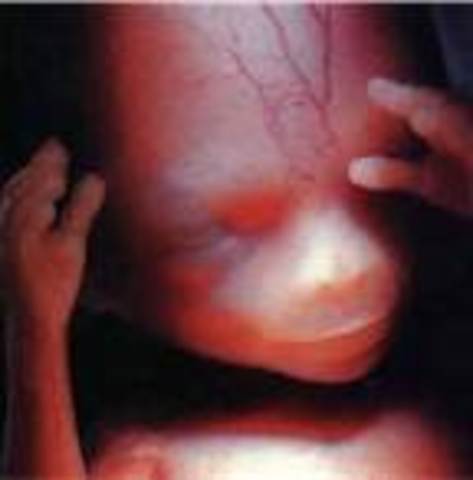

• Week 19

Week 19

I got it fromIf baby is female the uterus starts to develop, the vagina, uterus, and fallopian tubes are in place. Females have a limited supply of eggs in their lifetime. At this point your daughter will have 6 million eggs. This amount decreases to approximately one million by birth. If it's a boy, the genitals are distinct and recognizable. Even if the sex looks obvious, ultrasound operators have been known to make mistakes.